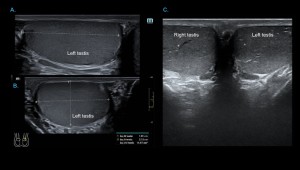

ULTRASOUND ANATOMY OF THE TESTES

The testes, suspended in the scrotum, are ovoid and obliquely oriented, with the left usually slightly lower. On ultrasound, adult testes measure 3–5 cm in length, 2–4 cm in width, ~3 cm anteroposteriorly, with an average volume of 15–20 mL.

- Grey-scale: adult testes show homogeneous, medium-level echotexture with smooth, well-defined margins.

Comprehensive evaluation includes grey-scale, colour, power, and spectral Doppler of the testes, epididymides, and scrotal contents.

Technique:

- Patient positioning: Supine, hips and knees flexed in external rotation; scrotum elevated on a folded towel; penis draped against the lower abdomen.

- Equipment: High-frequency linear transducer (7–14 MHz).

- Scanning planes: Longitudinal and transverse images of each testis; comparative transverse view at the midline for simultaneous evaluation.

- Parameters: Morphology, size, echogenicity, and vascular flow.

Initial assessment: Examine scrotal skin for symmetry, thickening, or edema. Start with the asymptomatic testis to optimize Doppler and compare findings with the contralateral side.